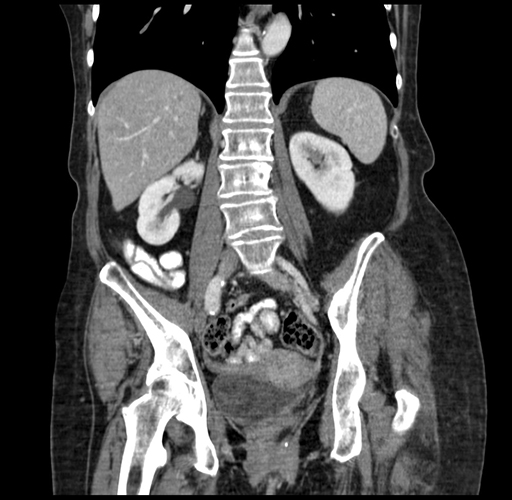

Pre-Chemo: Coronal Venous

Coronal Venous

Imaging analysis

Based on your CT findings, which issue(s) would give reason for "planned slowing down moment(s)" in this case?

Considering a standard right hepatectomy procedure, what step(s) of the operation would you do differently in this case?